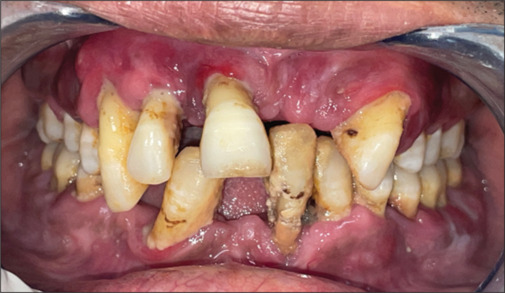

Langerhans cell histiocytosis (LCH) is a rare hematologic disorder characterized by the abnormal proliferation of Langerhans cells, resulting in a wide range of clinical manifestations and diagnostic challenges. A 36-year-old male presented with complaints of mobile teeth, gingival pain, and eczematous rashes on the toes. Clinical examination revealed advanced gingivitis, significant alveolar bone loss, and micronodular opacities in the chest on radiographic imaging. Histopathological and immunohistochemical analyses confirmed the diagnosis of LCH. This case underscores the diverse clinical spectrum of LCH and highlights the pivotal role of histopathology and immunohistochemistry in achieving a definitive diagnosis. Management strategies vary depending on the extent of disease involvement and may include surgical excision, corticosteroid therapy, or systemic chemotherapy. The case emphasizes the necessity of comprehensive evaluation and interdisciplinary collaboration in the diagnosis and treatment of rare disorders such as LCH.